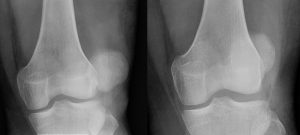

luxating patella